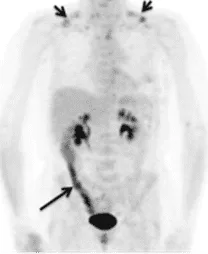

Estas molecular radioactivas, también conocidas como radiotrazadores, se fusionan con otras moléculas que nuestro cuerpo utiliza para permitir el seguimiento de su actividad fisiológica. Por ejemplo, el ya conocido isotopo del flúor se fusiona con una molécula de glucosa, generando el 18F-FDG. Al inyectar esta molécula al paciente, cualquier célula o actividad que necesite de glucosa tomará el 18F-FDG como fuente de azúcar.

Por este motivo, el uso de 18F-FDG se usa en PET para la detección de múltiples tipo de tumores, ya que estos consumen una gran cantidad de azucares para su rápido crecimiento; infecciones multisistémicas inflamatoria, que también necesitan un alto consumo de glucosa; enfermedades metabólicas en cerebro y pulmones, y por último para la detección de enfermedades cardiovasculares, como el infarto agudo de miocardio, ya que las células muertas del corazón no consumen glucosa y, por lo tanto, si no se observa este marcador en el corazón, se puede concluir la existencia de esta patología.